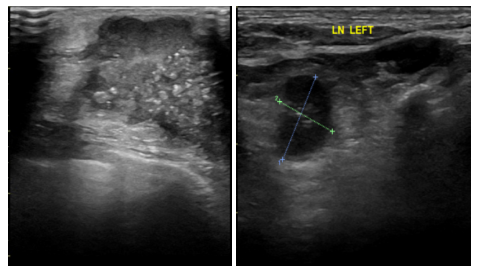

2021.6.9乳腺钼靶片提示:两侧乳腺呈不均匀致密型(ACRc),双乳腺体组织呈弥漫类结节改变。左乳外上象限见一分叶状肿块,边缘少许毛刺,大小约4.5cm×3.5cm,内见成簇细沙样钙化影,邻近皮下脂肪层见条索状密度增高、相应皮肤增厚,相应的乳后间隙部分显示欠清晰。右乳内未见明显异常密度结节或肿块形成,右乳内未见钙化灶。两侧腋下多发淋巴结显示(左腋下较多),双侧胸大肌未见异常,右乳皮肤、皮下、乳头、乳晕未见异常。

影像诊断:左乳外上象限占位(BI-RADS 5类),建议进一步检查;右侧乳腺增生(BI-RADS 1类);左侧腋下多发淋巴结显示。

图2.乳腺钼靶片(2021-6-9)